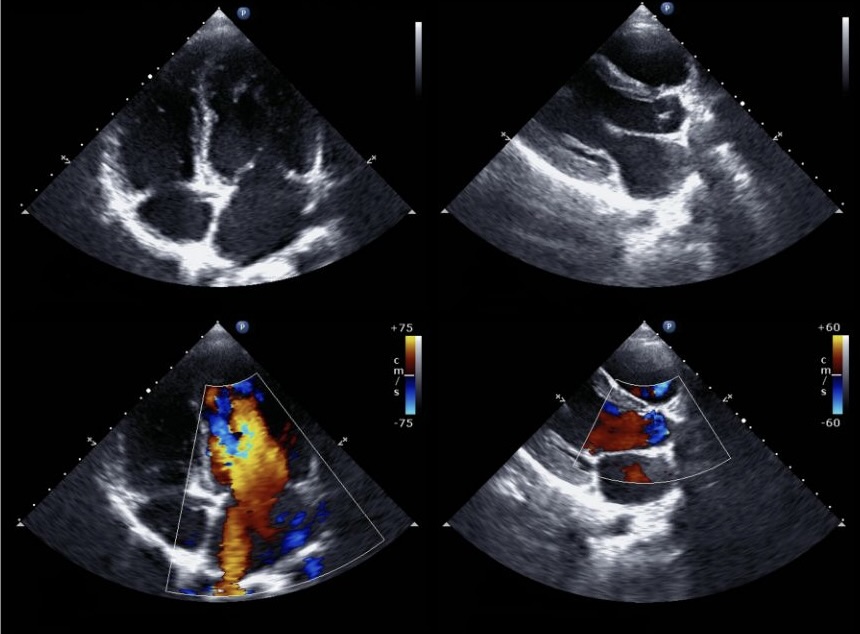

Eine frühzeitige Erkennung von Herzerkrankungen ist zur Vermeidung von Komplikationen wichtig. Regelmäßige Gesundheits- und Vorsorgeuntersuchungen ("Check-ups") können dabei helfen, potenzielle Probleme zu identifizieren, bevor sie ernsthafte Gesundheitsprobleme verursachen. In diesem Artikel stelle ich Ihnen Vorsorgeuntersuchungen vor, die zur frühzeitigen Erkennung von Herzerkrankungen beitragen können.

Die Wahrnehmung der empfohlenen Gesundheitsuntersuchungen ("Check-ups") in dreijährigen Abständen kann zur frühzeitigen Diagnostik von Herzerkrankungen beitragen, wie ich es während meiner hausärztlichen Tätigkeit bereits viele Male feststellen konnte. Alle vorgenannten Untersuchungsverfahren sind in unserer Praxis verfügbar. Falls nicht schon geschehen, planen Sie Ihren nächsten Vorsorgetermin zum Wohle Ihrer Herzgesundheit.